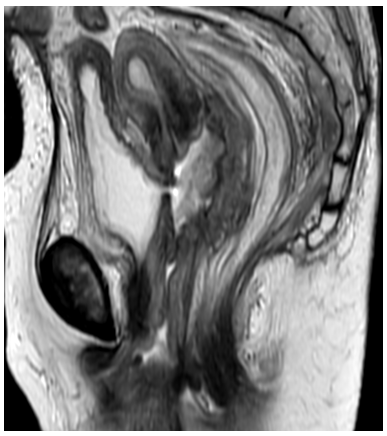

Uro-Genital and Genito-Digestive Fistulas Following Radiation in Cervical Cancer: A Study of 30 Cases